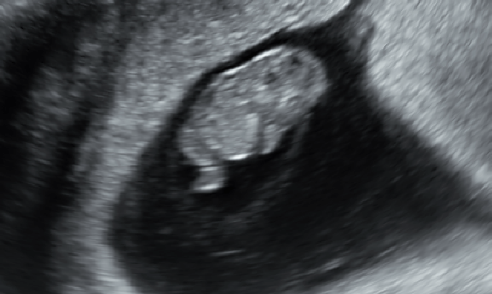

미성숙난자채취 시험관아기시술 후 졸업

7-8년전부터 생리불순이 있어 2020년부터 난임치료를 시작했던 30대 중반의 환자분입니다. 난임검사 상 양...